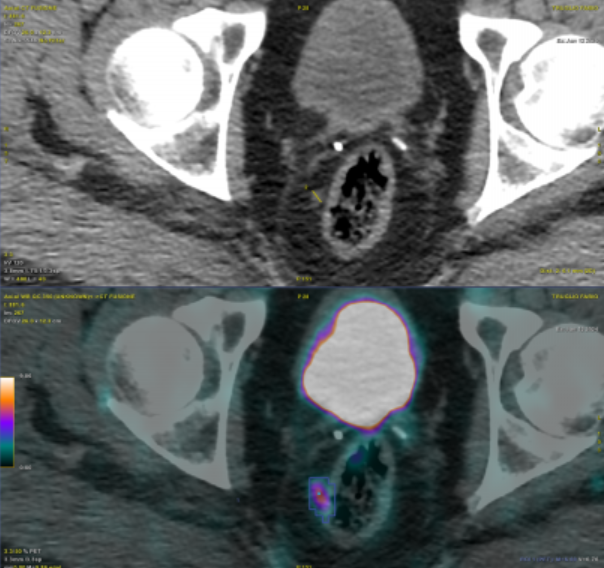

Long-term disease-free survival and health-related quality of life results of HDR brachytherapy as monotherapy pubmed.ncbi.nlm.nih.gov/39547869/

Long term outcomes for prospective trial of HDR monotherapy - very reassuring outcomes, despite most patients not being MR-staged at the time